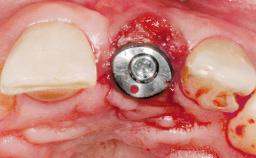

A 30-year-old female patient had lost tooth 21 and was referred to our clinic for consultation and treatment. Due to advanced apical infection, tooth 21 had been extracted two months earlier at another clinic and an acrylic-resin tooth had been bonded to the adjacent teeth. The patient desired implant treatment to avoid any damage to the adjacent natural teeth. While the patient had no history of any systemic disorder, she was a heavy smoker and exhibited medium to advanced periodontitis in the entire jaw. After the initial treatment to achieve a pocket probing depth of less than 4 mm and no bleeding on probing, a decrease in the height of the papillae mesial and distal to the extraction site and overall gingival recession were observed.

Type of Implants One-Piece|Reduced-Diameter

Bone Augmentation Horizontal|Staged

Augmentation Materials Autogenous chips|Membrane

Soft Tissue Grafting Simultaneous